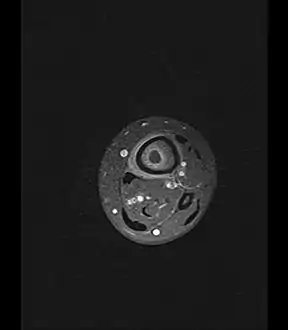

Axial T1-weighted fat-saturated MRI image following IV gadolinium contrast demonstrating the intramedullary lytic area seen on radiography to be ring enhancing consistent with a purulent fluid collection. Extensive circumferential periosteal enhancement is noted. There is also substantial bone marrow enhancement.